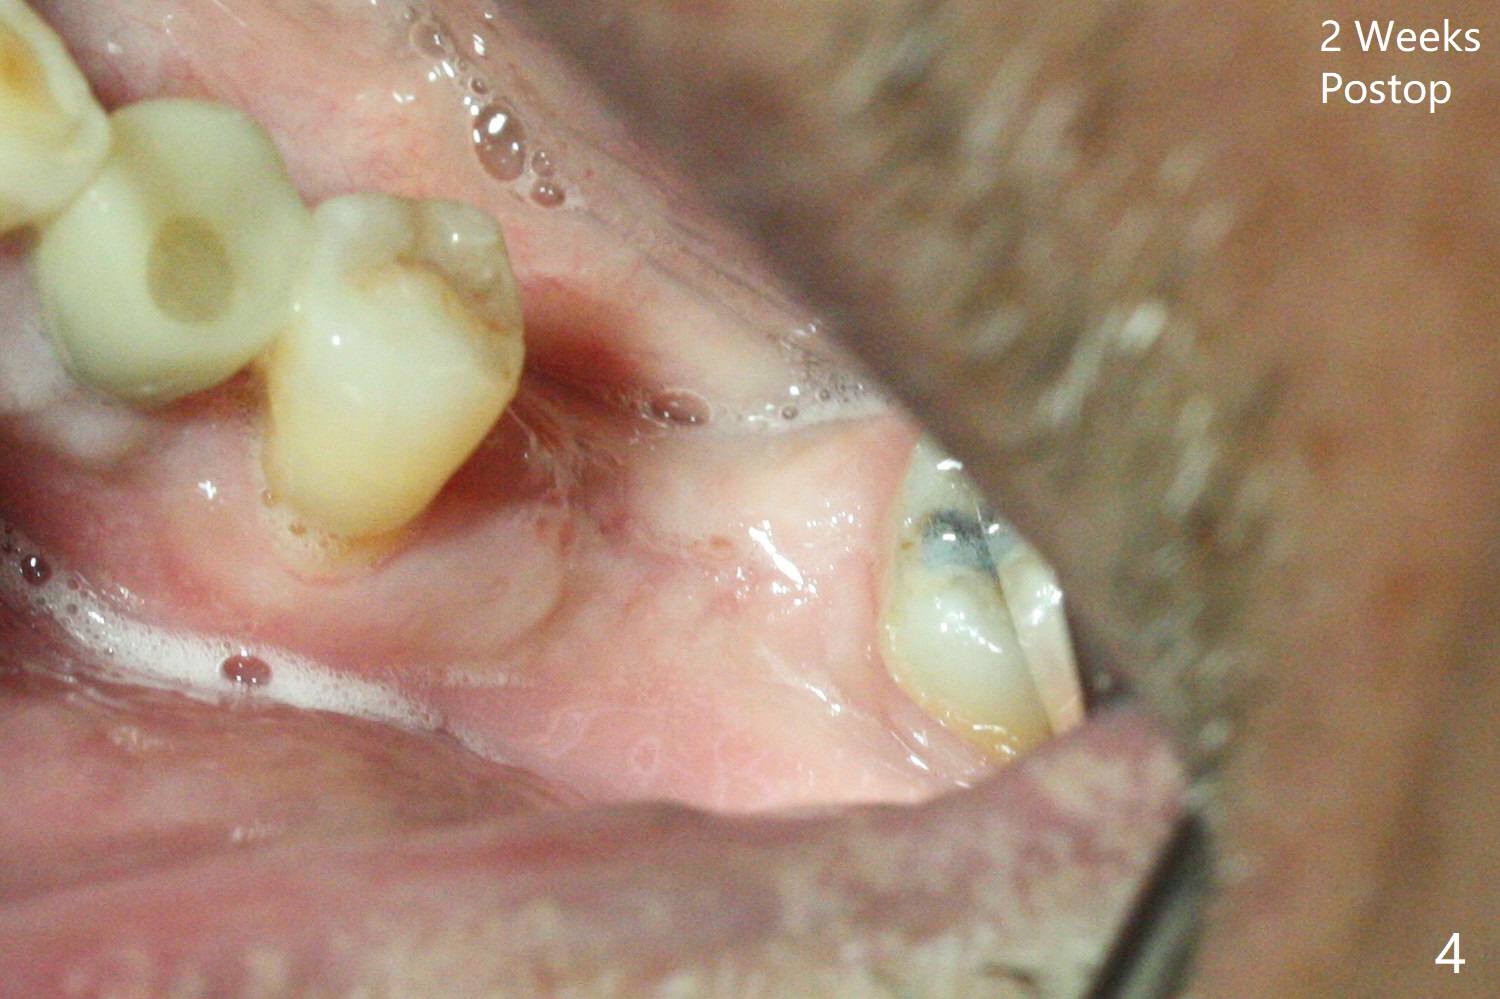

左下6,7导板设计种植两个小植体,牙槽嵴角化龈狭窄(图一:*),切开,钻洞,6处骨质密度高,钻头与植体直径必须一样,但是为了保证稳定性,最后1.5毫米钻头小0.5毫米,植体最后1-2毫米必须倒旋一次才能控制扭力不超过40Ncm,术后即刻根尖片显示4,6根尖部(密度2200单位,图二)螺纹弯曲(<),而7(密度670单位)钻头比植体小0.5毫米,植入扭力也大约40Ncm,不过螺纹没有变形。祸不单行,6植体冠部舌侧螺纹暴露约1毫米,放入自体骨后,盖膜(6个月),4-0铬羊肠线减张缝合(图三),牙槽嵴好像增宽了。术后两周伤口愈合(图四)。术后4.5个月切开暴露,尽管需要外科钻头去除植体冠部骨质,6舌侧植体螺纹仍暴露,放置4.5x3毫米愈合基台,7放置4x4(3)毫米修复基台(图五),但是接近8牙冠,无法修复,必须做局部牙齿矫正。术后7个月7放置3.4x3毫米愈合帽,6放置4.5x5.7(4)毫米修复基台,手拧紧,做临时牙冠,垫高,开始矫正;一个月后基台松动,扳手拧紧(30Ncm);7处3.4x3毫米愈合帽没有就位,由于远中牙槽嵴阻挡(图六:<)。